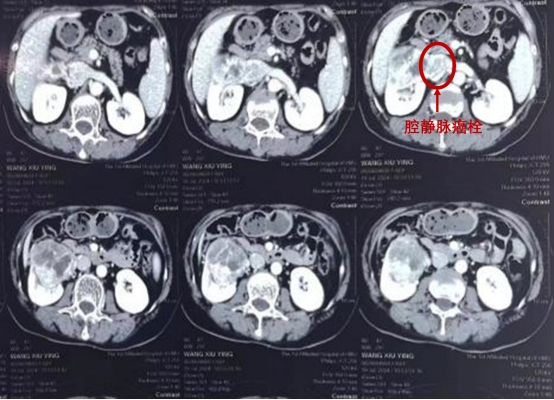

古稀之年的张大爷因血尿就诊,发现右肾巨大肾癌伴肾静脉癌栓,几经辗转,找到ac米兰官网中文网站一院修有成教授。住院后详细检查,发现右肾肿瘤不仅巨大,而且肾静脉、腔静脉已经被肿瘤侵袭,充满癌栓。修有成教授介绍,传统手术切除患肾远远不能达到要求,需要将人体最大的静脉--腔静脉临时阻断后切开,然后将癌栓完全取出才能达到更好的收益。

刘赞教授介绍,肾癌根治术虽现已成熟,但静脉癌栓,尤其是腔静脉癌栓,手术需要将血管切开,将癌栓取出后用血管缝合线缝合血管。而腔静脉作为人体最大的静脉,在手术分离、阻断、缝合每一个手术步骤中,一旦出现失误,势必会出现术中大出血,危及生命。血管手术对于泌尿外科医生来讲,一度被认为是手术禁区。